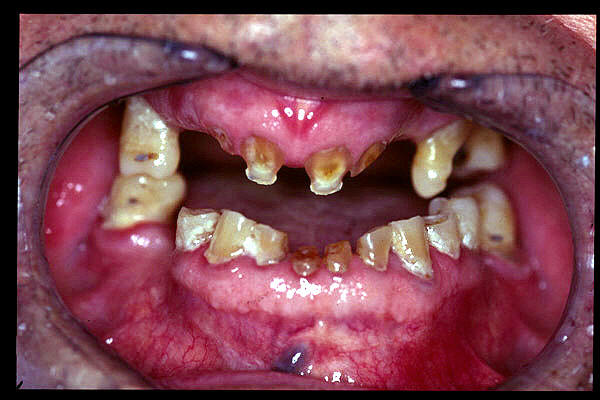

CM Caries y enfermedad periodontal avanzada